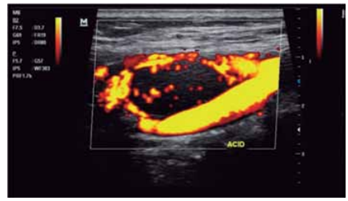

Observe a imagem a seguir.

A imagem ultrassonográfica apresentada corresponde a qual diagnóstico?